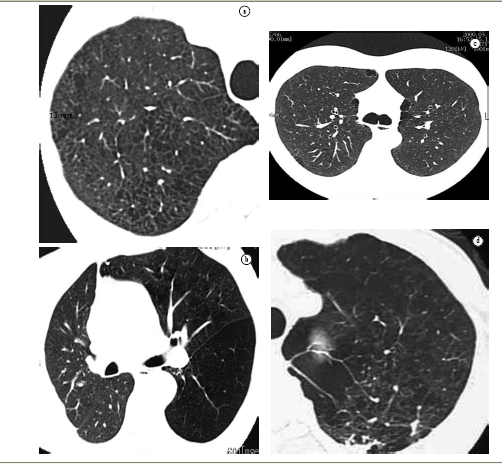

In contrast to conventional chestX-ray,computed tomography (CT) has proven very sensitive and specific in the evaluation of emphysema.(14,23-43)Since findings were first described in 1982,(14) CT has been used to detect, characterize and quantify the disease. Centrilobular emphysema is characterized by the presence of low attenuation areas, with ill-defined margins, generally without visible walls.(44) Lesions present a 'moth-eaten' appearance. When emphysematous lesions reach diameters greater than those of the lobes, part of their diameters can become well-defined, mimicking cysts, due to the presence of interstitial septa or major vessels surrounding the lesions. In a study that evaluated various signs of centrilobular emphysema, low attenuation areas in the medulla portion of the lungs, revealed on CT scans, correlated significantly with emphysema evaluated post mortem.(45) Other signs of emphysema include bullae (pseudocysts that contain air, with thin well-defined walls), rarefaction of vessels and distortion of the vasculature. Complementary signs of hyperinflation of the lungs that, when pronounced, are promptly identified on chest X-ray, might not be so obvious on CT. However, the anterior joint line of the lungs, measuring 3 cm in the anteroposterior portion, suggests hyperexpansion in the patient with emphysema.(46)

The high-resolution CT (HRCT) can differentiate among the various types of emphysema, in patients with mild or moderate disease,(47) depicting with great similarity the findings of pathological anatomy described above, according to which centrilobular emphysema presents: preference for upper thirds,(45) and it can be confined to these regions; low density multifocal areas resulting from the destruction of the alveoli, predominantly in the medullar portion, distant from the pleura(45); lesions that can be similar to small cystic air spaces, typically without an obvious wall; and lung surrounding lesions, which can be totally normal. With the progression of the disease, centrilobular emphysematous lesions become confluent.

HRCT, in panlobular emphysema, reveal a more uniform pulmonary destruction, with extensive low density areas, accompanied by vascular distortion and rarefaction. In classical panlobular emphysema, small focal low density areas, characteristic of centrilobular emphysema, are not found. In contrast to the latter, distribution is preferential in the lower thirds of the lungs.

Paraseptal emphysema is easily detected on HRCT scans, and presents as low density areas, with well-defined, hair-thin walls.(48) These pseudocysts are distributed in the subpleural regions or adjacent regions to larger bronchovascular cuffs. This emphysema pattern curiously have a 'saw-tooth' appearance and, occasionally, interstitial septa can seem particularly prominent; sometimes, they can mimic lymphangitic carcinomatosis at chest X-rays, which is promptly revealed on HRCT scans.(48)